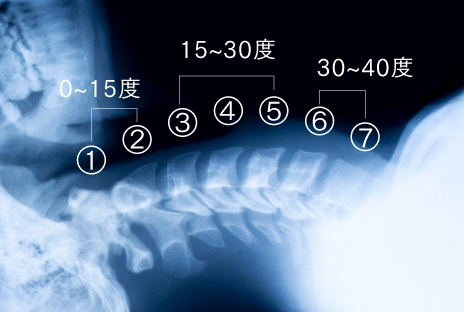

頸椎の牽引においては、頸椎が第一から第七までの7個の骨で構成されているため、全ての頚椎に正しくアプローチするには、40度以上牽引することが重要です。